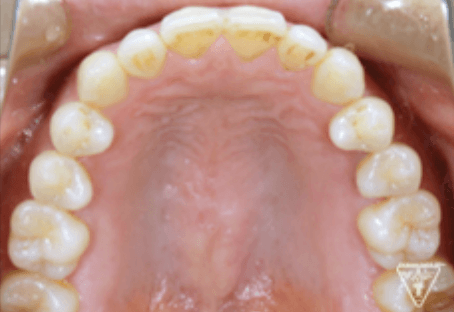

治療過程②